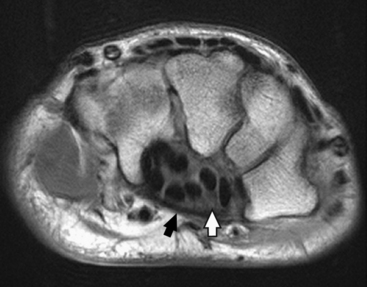

The body of the ulna is long and slender and tapers inferiorly. The upper portion of the ulna is large and presents two beaklike processes and concave depressions (Fig. 4-6). The proximal process, or olecranon process, concaves anteriorly and slightly inferiorly and forms the proximal portion of the trochlear notch. The more distal coronoid process projects anteriorly from the anterior surface of the body and curves slightly superiorly. The process is triangular and forms the lower portion of the trochlear notch. A depression called the radial notch is located on the lateral aspect of the coronoid process.

Fig. 4-6 A, Radial aspect of left proximal ulna. B, Sagittal MRI of elbow joint showing trochlear notch surrounding trochlea of humerus. (B, Modified from Kelley LL, Petersen CM: Sectional anatomy for imaging professionals, ed 2, St Louis, 2007, Mosby.)